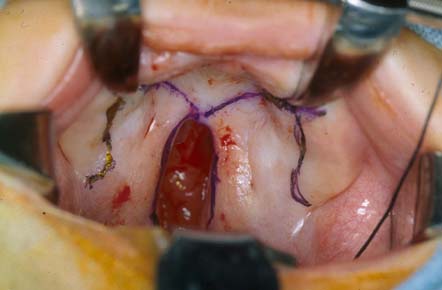

A palatoplastia pode ser realizada como um reparo de 1 estágio ou de 2 estágios (raramente), e é realizada através da criação de retalhos de tecidos orais do palato e a rotação desses retalhos palatais para permitir o fechamento de 3 camadas (camada da mucosa oral, dos músculos do palato mole e nasal).

A técnica de 2 retalhos é a base da palatoplastia unilateral, com a adição de uma dissecação de vômer (componente ósseo do septo nasal inferior à placa perpendicular do etmoide e posterior à cartilagem quadrangular do septo nasal anterior) na palatoplastia bilateral. Uma fenda palatina secundária menor é fechada usando-se uma Z-plastia de von Langenbeck, 3 retalhos (pushback, Veau-Wardill-Kilner) ou dupla oposição de Furlow, dependendo da preferência do cirurgião.[56][57][58][Figure caption and citation for the preceding image starts]: Reparo de fenda palatina mostrando desenho de von LangenbackDe: Senders CW, Sykes JM. Cleft palate. Em: Smith JD, Bumsted RM, eds. Pediatric facial plastic and reconstructive surgery. New York, NY: Raven Press; 1993:162 [Citation ends].

A técnica de 2 retalhos é realizada da seguinte forma: após o palato ser marcado com o desenho escolhido, o retalho da mucosa oral sofre incisão até os ossos palatinos e é elevado em um plano subperiosteal. Os vasos maiores do palato são preservados e os retalhos são mobilizados para permitir que as camadas orais entrem em contato uma com a outra medialmente. Os músculos do palato mole (tensor do véu palatino e elevador do véu palatino) são dissecados para permitir o fechamento sem tensão após as camadas nasais sofrerem incisão e serem fechadas. Suturas absorvíveis são usadas no fechamento, com atenção dada para minimizar a tensão nas linhas de sutura pela mobilização apropriada do retalho.[Figure caption and citation for the preceding image starts]: Reparo de fenda palatina mostrando desenho de palatoplastia com 2 retalhosDe: Senders CW, Sykes JM. Cleft palate. Em: Smith JD, Bumsted RM, eds. Pediatric facial plastic and reconstructive surgery. New York, NY: Raven Press; 1993:162 [Citation ends].